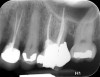

Clinical procedure: Once a perforation occurs, the extent of the perforation must be assessed. If there is an adjacent bony defect, the bony defect should first be filled with an osteoconductive or osteoinductive material. This can be done with a bone graft, calcium sulfate, or collagen/gelatin sponge. The dentinal portion of the tooth that has been perforated is then restored with MTA (Figure 9 through Figure 14).

Fig 9 Preoperative radiographs showing mesial perforation.

Figure 9

Fig 10. Preoperative radiographs showing mesial perforation.

Figure 10